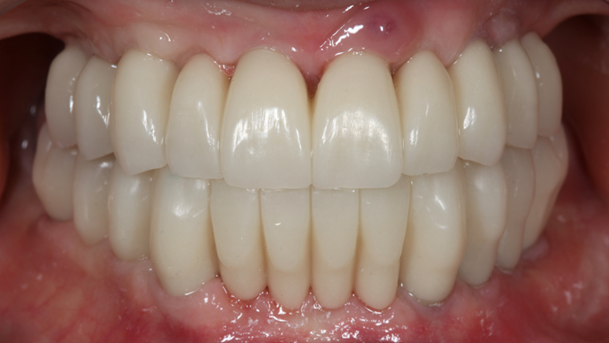

- Courtesy of Dr. Jong Cheol Kim, Korea